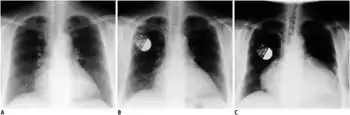

A chest X-ray might depict pleural effusion, pulmonary infiltration, or pericardial effusion.[2]